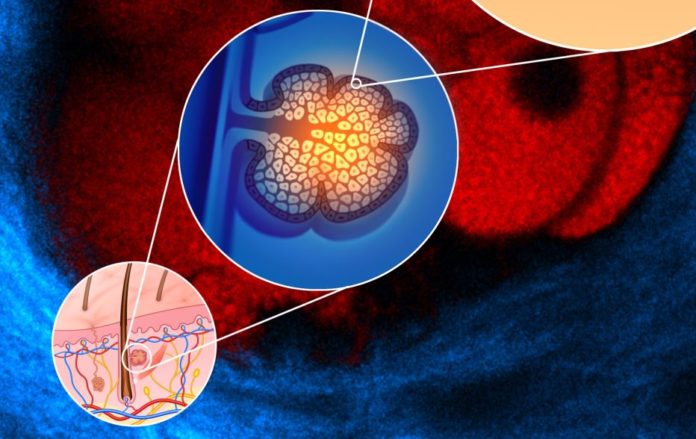

“La sindrome di Clouston è causata da mutazioni del gene GJB6 che fornisce le istruzioni per produrre la connessina 30 (Cx30), una proteina che si trova in diversi tessuti in tutto il corpo, inclusa la pelle, specialmente sul palmo delle mani e della pianta dei piedi, follicoli piliferi e letti ungueali, e svolge un ruolo nella crescita e nello sviluppo di questi tessuti”, spiega Fabio Mammano. “Le mutazioni del gene GJB6 che causano la sindrome cambiano i blocchi costitutivi di singole proteine, gli aminoacidi, nella Cx30. Sebbene gli effetti di queste mutazioni non siano completamente compresi, portano ad anomalie nella crescita, divisione e maturazione delle cellule nei follicoli piliferi, unghie e pelle”.

La sindrome di Clouston, conosciuta anche come displasia ectodermica idrotica, è una malattia ereditaria caratterizzata da anomalie dei capelli (alopecia), delle unghie (distrofia ungueale) e della pelle (ipercheratosi palmoplantare); aree della pelle, in particolare sopra le articolazioni, che sono di colore più scuro rispetto alla pelle circostante (iperpigmentazione); e punte delle dita allargate e arrotondate (clubbing). Attraverso questo studio i ricercatori hanno potuto esaminare l’efficacia di un potente anticorpo che agisce sulla connessina.